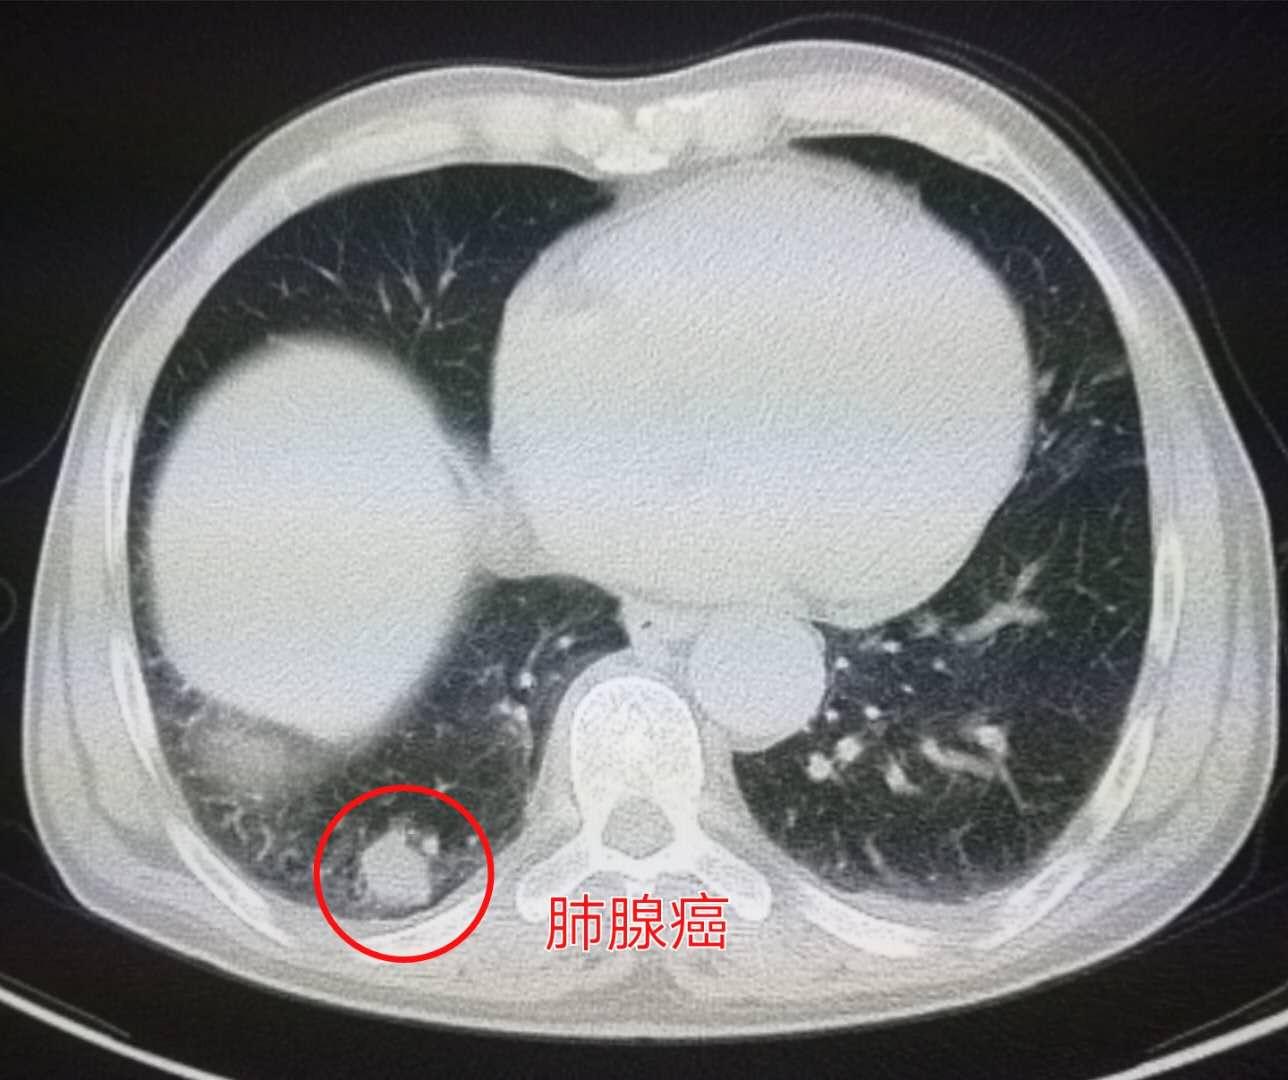

下图这位49岁的女性,说是最近记性不好,老忘事儿,以为是到更年期了?提前脑萎缩了?

神经内科医生说,做个脑CT看看吧:

结果发现了脑多发转移瘤。

紧接着做了胸部CT,发现左侧肺癌,肿瘤贴近胸部已经侵犯胸膜: